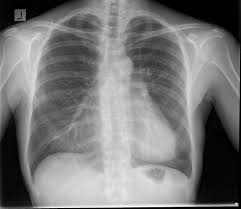

Fractured Sternum Injury Boston Chest Injury Lawyer

Fractured Sternum Injury Boston Chest Injury Lawyer from burnsjainlaw.com